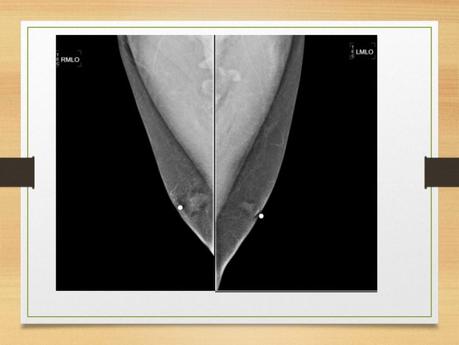

•PROYECCIONES MAMOGRAFICA •M.A.M FRANCISCO GUILLERMO COSME VASQUEZ. •17-ENE-2019 •Proyecciones mamográficas •Un buen posicionamiento conlleva a una buena interpretación radiológica. •La dosis promedio glandular no debe exceder de 3 mGy. •Las imágenes mastograficas no deben presentar defecto alguno. •Imágenes de calidad requieren técnicos altamente motivados. • •El numero de proyecciones hoy en día pueden ser clasificados en tres categorías: •A) proyecciones estándar utilizadas en el tamizaje: cc y mlo •B) las proyecciones que ubican la posición exacta de una anormalidad en la mama. •C) proyecciones utilizadas para definir la naturaleza de la anormalidad •Posiciones •Sentada o de pie. •Pendular: inclinada hacia adelante. •prono. •El brazo colgado hacia adelante: relaja el m. pectoral mayor. • • •La mama debe comprimirse hasta que el tejido este tenso •Tocar la mama por un costado •La piel no debe hundirse •La compresión no debe ser dolorosa •Compresión •Proyecciones básicas •Craneocaudal (cc) •Oblicua mediolateral (OML) • •Craneocaudal •Colocar la mama medial •Elevar pliegue inframamario, ajustando la altura del receptor. •Usando ambas manos jalando y colocando encima del receptor •Muestra las partes interna y externa de la mama. •Se obtienen imágenes de ambas mamas por separado. •Paciente de pie o sentada. • •Se levanta la mama para lograr un ángulo de 90° con la pared torácica. •Se tracciona la mama hacia adelante con el pezón de perfil. •El brazo del lado evaluado se debe relajar, con el hombro hacia atrás. •La cabeza es girada lejos del lado evaluado. •Dejar la mama opuesta sobre la esquina del receptor •Px inclinada hacia delante, con la cabeza hacia un costado del tubo. •La piel debe deslizarse sobre la clavícula •Jalar el tejido lateral sin perder tejido medial • •Una proyección óptima requiere: •A) visualizar las porciones externa e interna de la mama, •B) Visualizar grasa de Chaissagnac •C) Visualizar el pectoral mayor •D) Visualizar el pezón bien alineado. • •Oblicuo medio lateral •Paciente de pie o sentada. •Ambas mamas por separado. •El rayo central entra perpendicular al músculo pectoral de la paciente. •Se debe determinar el grado de oblicuidad del musculo pectoral entre 45 y 60 grados. • • • •La paciente de frente al mastógrafo, coloca el brazo del lado evaluado hacia adelante y la mano hacia el frente. •Se tracciona la mama y el m. pectoral anterior y medialmente, lejos de la pared torácica. •Aplicar compresión con la mama lejos de la pared torácica y hacia arriba. •El borde superior debajo de la clavícula y el borde inferior incluirá el pliegue infra mamario •La paciente puede retraer la mama opuesta con la otra mano. • • •Criterios de evaluación: • a) Debe verse todo el tejido mamario •b) el musculo pectoral se debe encontrar a la altura del pezón •c) el patrón del parénquima debe observarse a 90 grados •d)Demostrar pliegue inframamario •e) región axilar visible •f) pezón perfilado •g) área glandular y adiposa adecuadamente penetradas. •Proyecciones especiales •Lateral a 90 grados •Cono de compresión •Magnificacion •Craneocaudal exagerada •Escote •Cola axilar •Tangencial •giro • •Mediolateral •Útil en patologías en la cara central o lateral de la mama. Para confirmar una anomalía observada en la OML. •calcificaciones •Aire •Niveles de liquido •Localizar lesiones en plano sagital •Eliminar sobreposiciones •De pie o sentada. •El RC es angulado a 90°. • • •La paciente frente al mastografo coloca el brazo del lado a examinar hacia adelante la mano sobre la barra hacia el frente. •Se tracciona la mama y el m. pectoral anterior y medialmente. El pezón de perfil. •Aplicar compresion. •Traccionar el tejido abdominal hacia abajo. •La paciente retrae la mama contralateral con la mano opuesta. • •La imagen debe incluir todo el tejido mamario, •la region axilar y •el m. pectoral. • •Craneocaudal exagerada (lateral CCEL) •Es la proyeccion mas solicitada cuando la CC no muestra todo el tejido axilar o cuando se observa una lesion en la OML pero no en la CC. •Se inicia como una CC, luego se rota el cuerpo ligeramente para incluir mas axila. •La mano al frente, relajar el hombro. •La cabeza lejos del lado a explorar. •Si la lesión es lateral se debe tomar una CCE medialmente. •Craneocaudal exagerada (lateral CCEL) •Es la proyeccion mas solicitada cuando la CC no muestra todo el tejido axilar o cuando se observa una lesion en la OML pero no en la CC. • •Proyección con desplazamiento de implante (Ecklund) •Lesiones subyacentes al implante. •Complicaciones como pérdida intracapsular o extracapsular del implante. •No puede lograrse una compresión firme. •Se realiza después de las proyecciones básicas. •El método de Eklund consiste en empujar el implante hacia la pared torácica. • •Proyección axilar •Se usa para aislar la cola axilar y cualquier lesión dentro de esta. •El tubo se debe colocar paralelo a la axila. •Los tejidos laterales se incluyen en el campo de la imagen. •Solo se comprime la cola de la mama. • • •Proyección del surco •Visualiza el tejido y la porción mas medial de los cuadrantes internos. •Se colocan las dos mamas en posición horizontal. •Se aplica compresión. • •Cono de Compresión •Reduce el grosor de un área en específico. •Se realiza en la proyección donde se observa la lesión en estudio. Se mide la distancia de la lesión al pezón. •Se aplica los platos pequeños para realizar la compresión. •Generalmente se combina con magnificación •Magnificación •Agrandar áreas específicas de interés •Lesiones pequeñas •Microcalcificaiones. •Tubo de rayos x con un foco de 0.1mm •Agrandamientos de 1.5 a 2 veces •Se puede utilizar en la mayoría de las proyecciones mamográficas. •Magnificación •Se acerca el foco a la mama alejando el detector. •Se puede realizar en todas las proyecciones. •Se efectúa para compresión focal o localizada • •Mama masculina •Posición de la mama masculina •Se coloca similar a una mama femenina pequeña. •La OML se usa para obtener imágenes en proyección lateral. •La CC se puede hacer caudocraneal. • • • • •